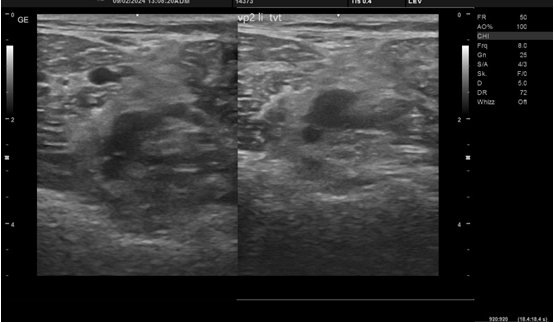

Eine tiefe Venenthrombose entsteht dann, wenn sich ein Thrombus (Blutgerinnsel) in einer Vene bildet. Meست passiert dies in den Beinen, in seltenen Fällen kann eine TVT allerdings auch in den Armen auftreten. Durch dieses Blutgerinnsel wird die Vene verstopft und das Blut kann nicht mehr richtig durch die Vene laufen. Es besteht bei einer TVT die Gefahr, dass sich der Thrombus löst und in die Lunge wandert. Dort würde dieser eine Lungenembolie auslösen. Zur Behandlung der TVT wird in den meisten Fällen eine Medikamentöse Behandlung mithilfe von Blutverdünnern (Eliquis, Xarelto, etc.) sowie eine Kompressionstherapie durch Maßangefertigte Kompressionsstrümpfe angewandt.